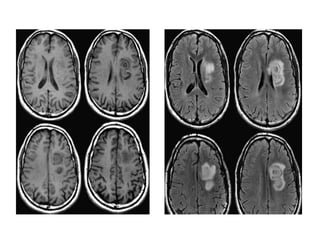

• The lesions in the deep white

matter (yellow arrow) are

nonspecific and can be seen in

many diseases.

Typical for MS in this case is:

• Involvement of the temporal

lobe (red arrow)

• Juxtacortical lesions (green

arrow) - touching the cortex

• Involvement of the corpus

callosum (blue arrow)

• Periventricular lesions -

touching the ventricles